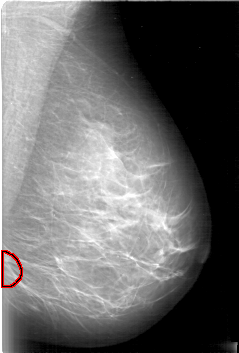

D_4006_1.LEFT_CC

LEFT_CC LINES 5296 PIXELS_PER_LINE 3421 BITS_PER_PIXEL 12 RESOLUTION 43.5 OVERLAY

FILE: D_4006_1.LEFT_CC.OVERLAY

TOTAL_ABNORMALITIES 1

ABNORMALITY 1

LESION_TYPE MASS SHAPE OVAL MARGINS OBSCURED

ASSESSMENT 0

SUBTLETY 5

PATHOLOGY BENIGN

TOTAL_OUTLINES 1

BOUNDARY